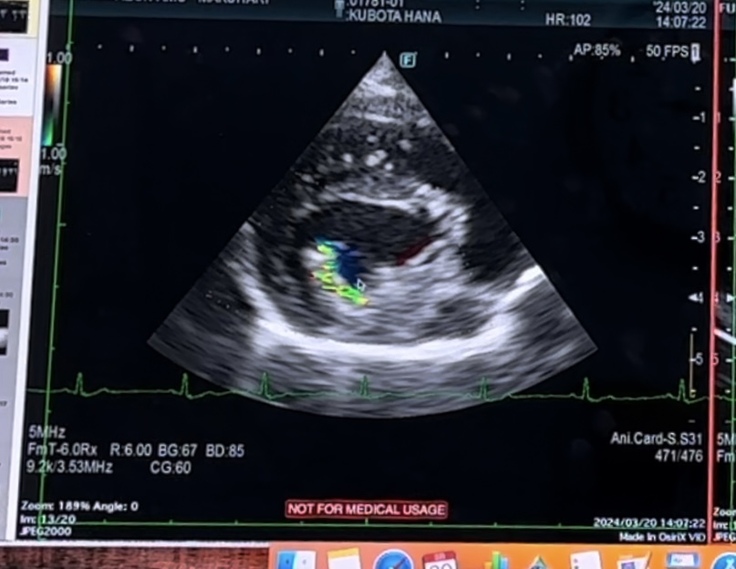

本日、心臓手術後 7ヶ月検診でした

心臓の方は

逆流の量は少し減った様にみえるが…

範囲が広くなったような印象…

との事で …また、来月、検査です…